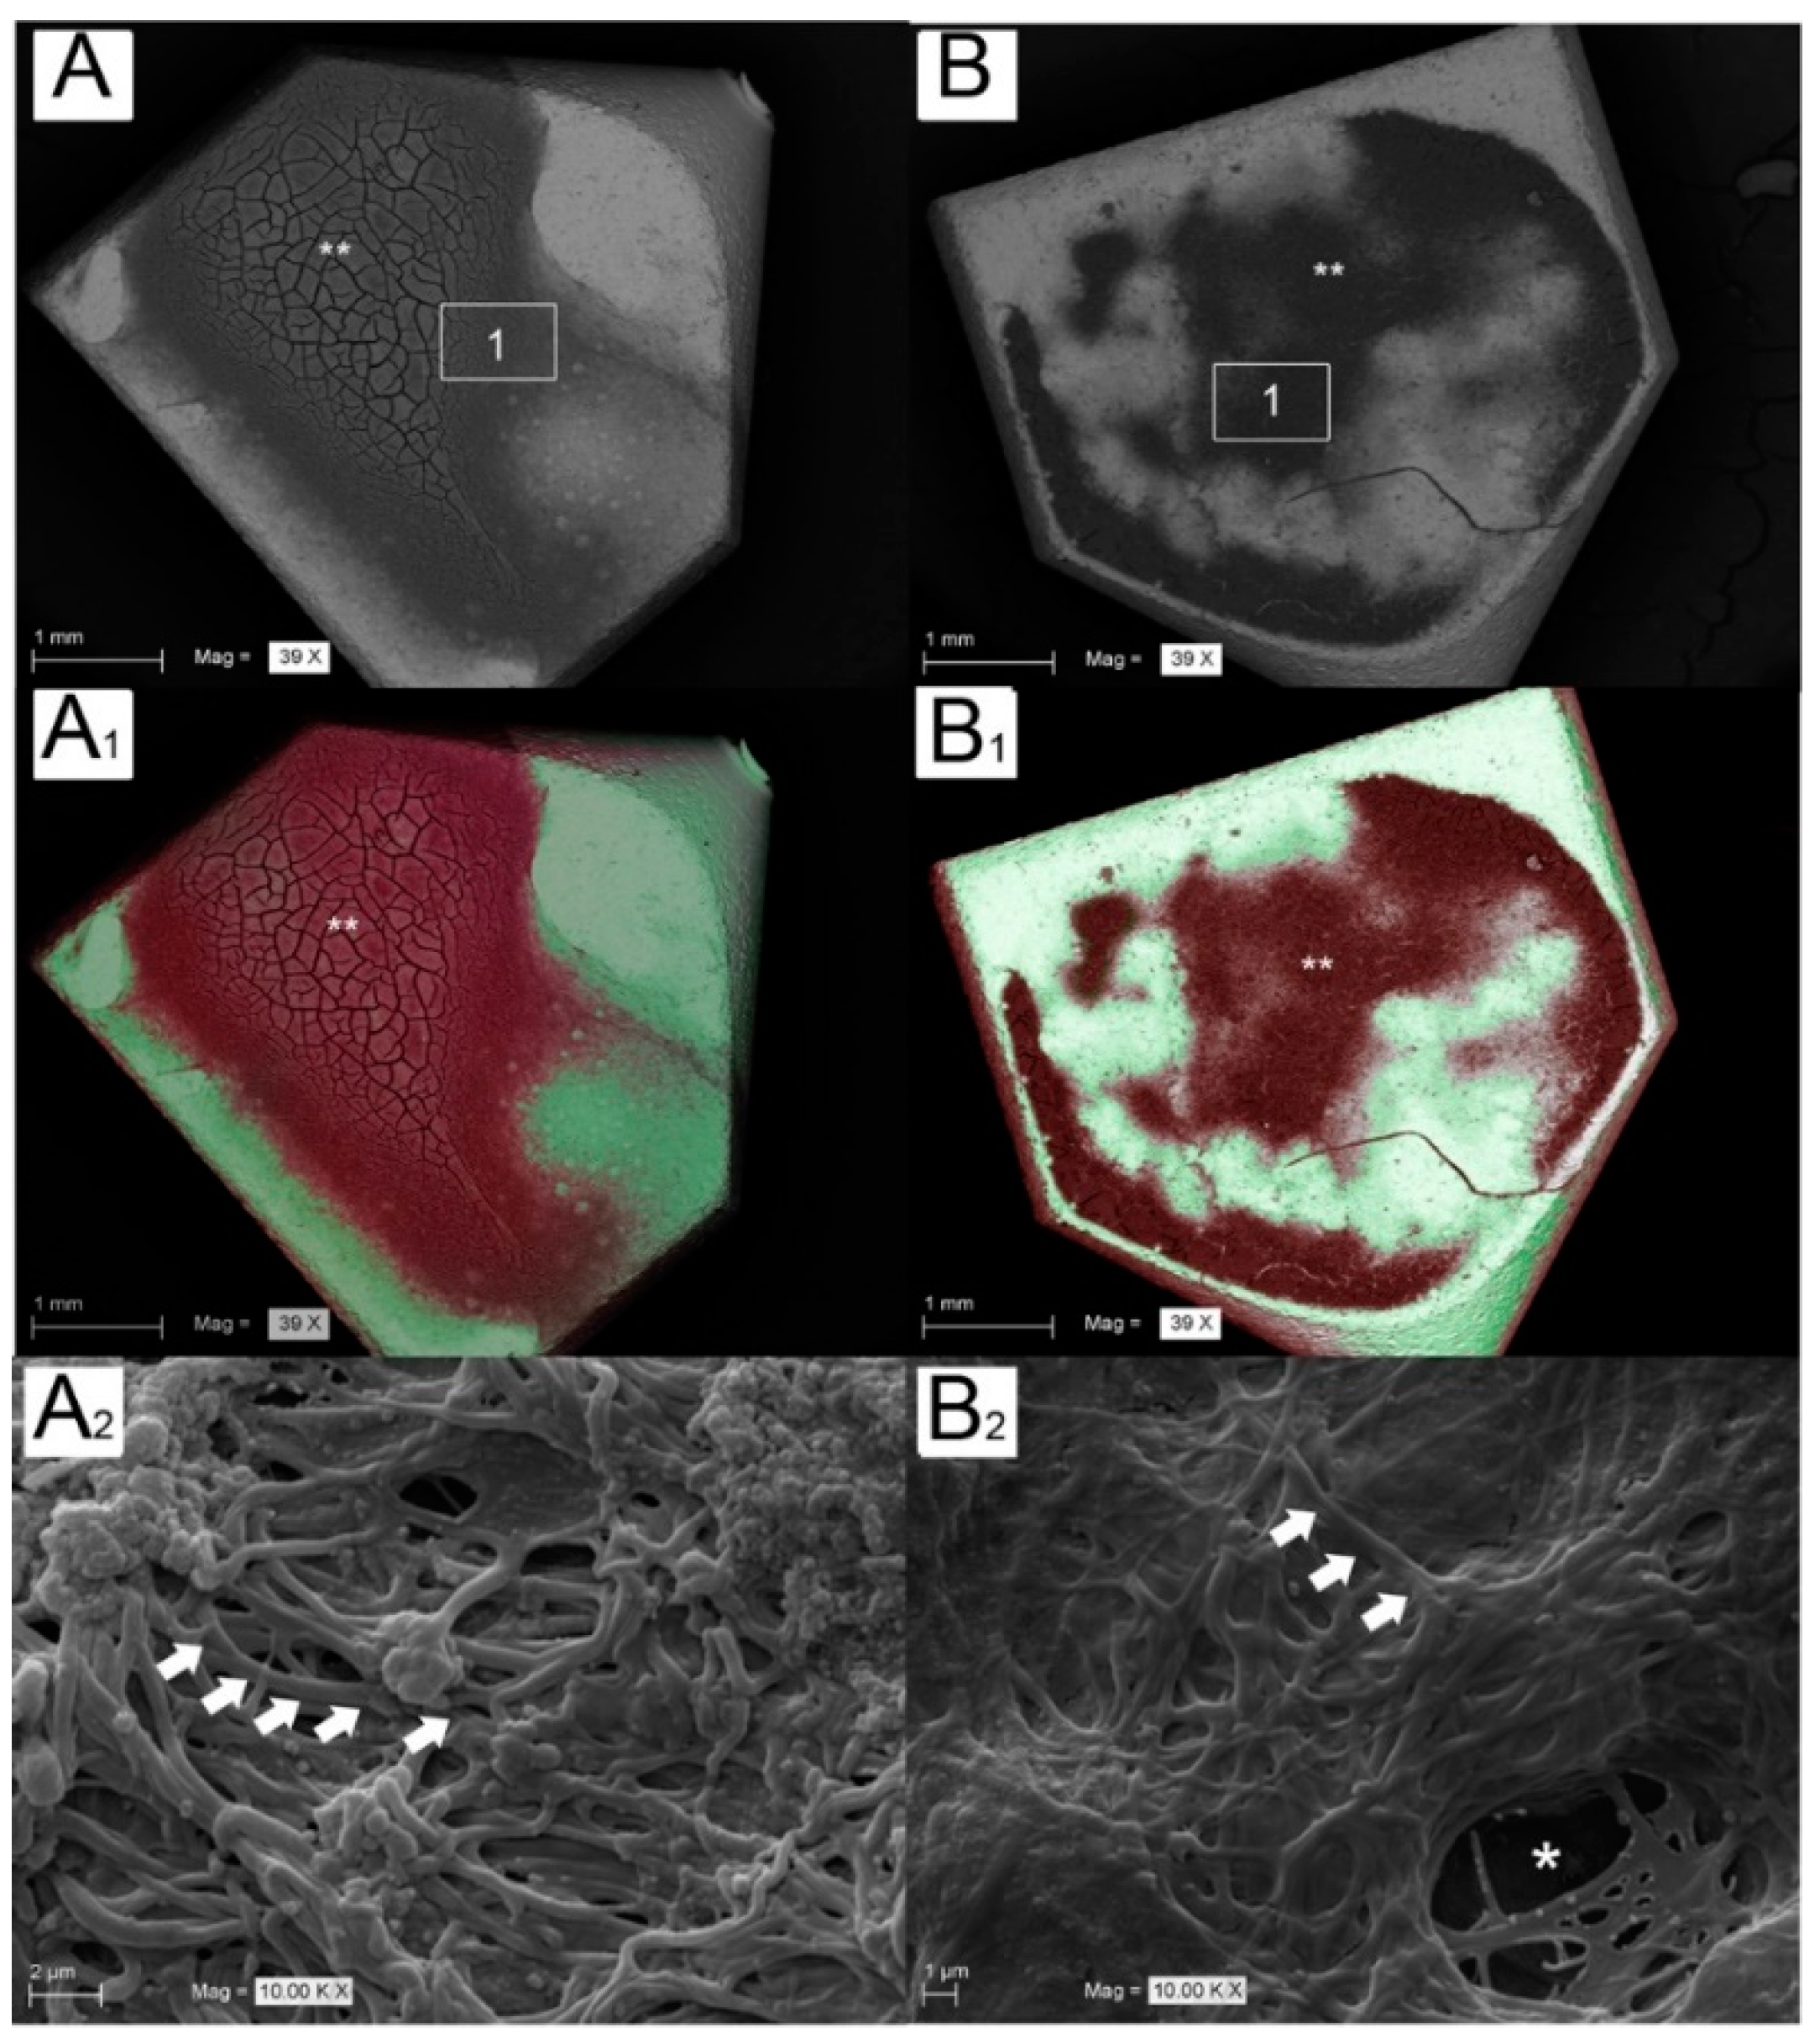

3.4. Blood Clot Extension